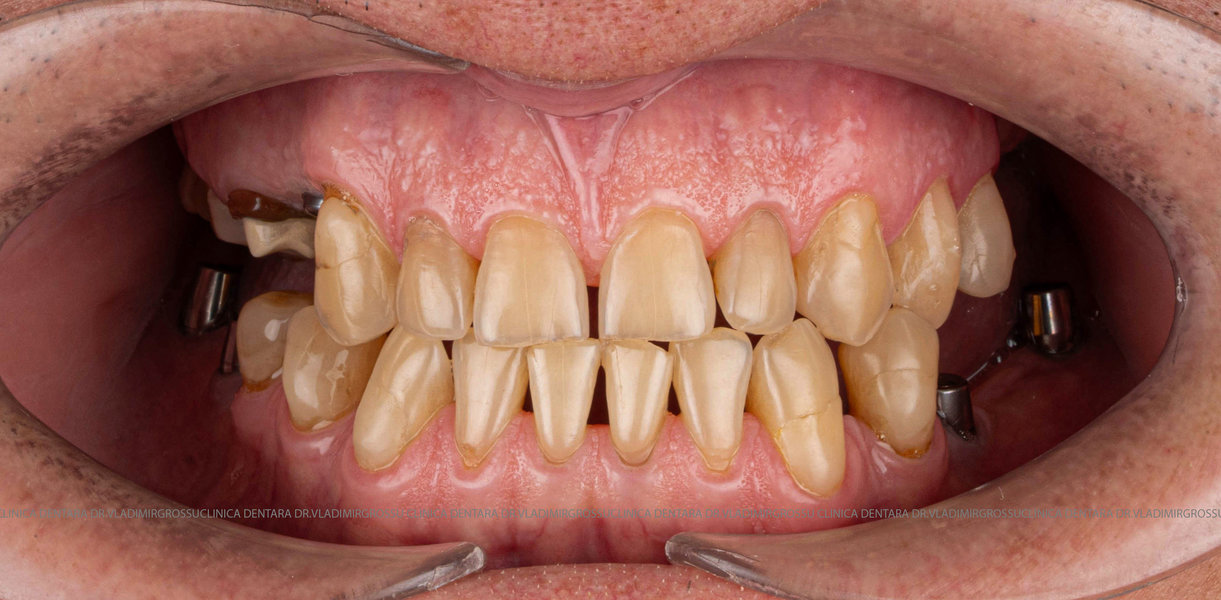

După inserarea unui implant dentar – o rădăcină artificială din titan sau zirconiu –, urmează etapa de protezare, adică atașarea unei structuri protetice (coroană, punte sau proteză) care înlocuiește dintele lipsă.

- Consultația inițială și planificarea tratamentului (inclusiv tomografie CBCT)

- Inserarea implanturilor dentare (chirurgie ghidată digital)

- Perioada de osteointegrare (3–6 luni)

- Amprentarea digitală sau clasică a zonei

- Proteze pe sistem de bare sau capse (All-on-4, All-on-6)